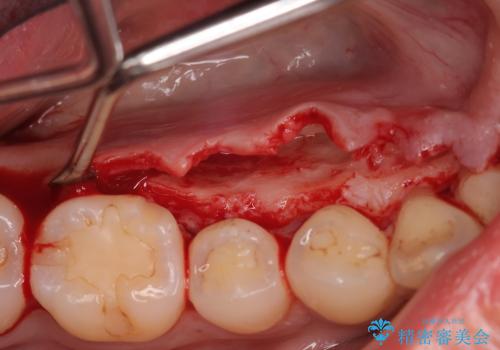

- 下顎の骨隆起を取りたいとのことで来院された患者様です。

一般的な歯科治療で用いる局所麻酔下で進めていきます。

右側と左側で2回に分けて行いました。

術後1週間での抜糸となります。